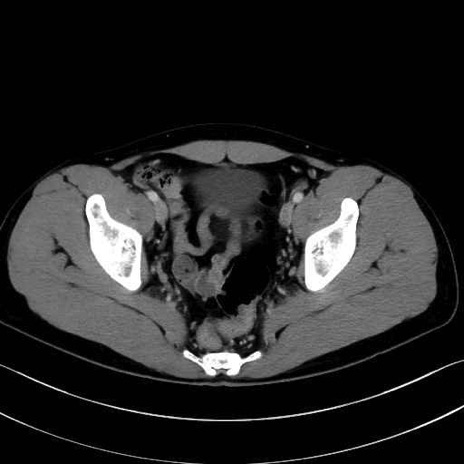

2. 腸腰筋群と骨盤底筋

腸骨筋 (Iliacus)

肛門挙筋 (Levator ani)